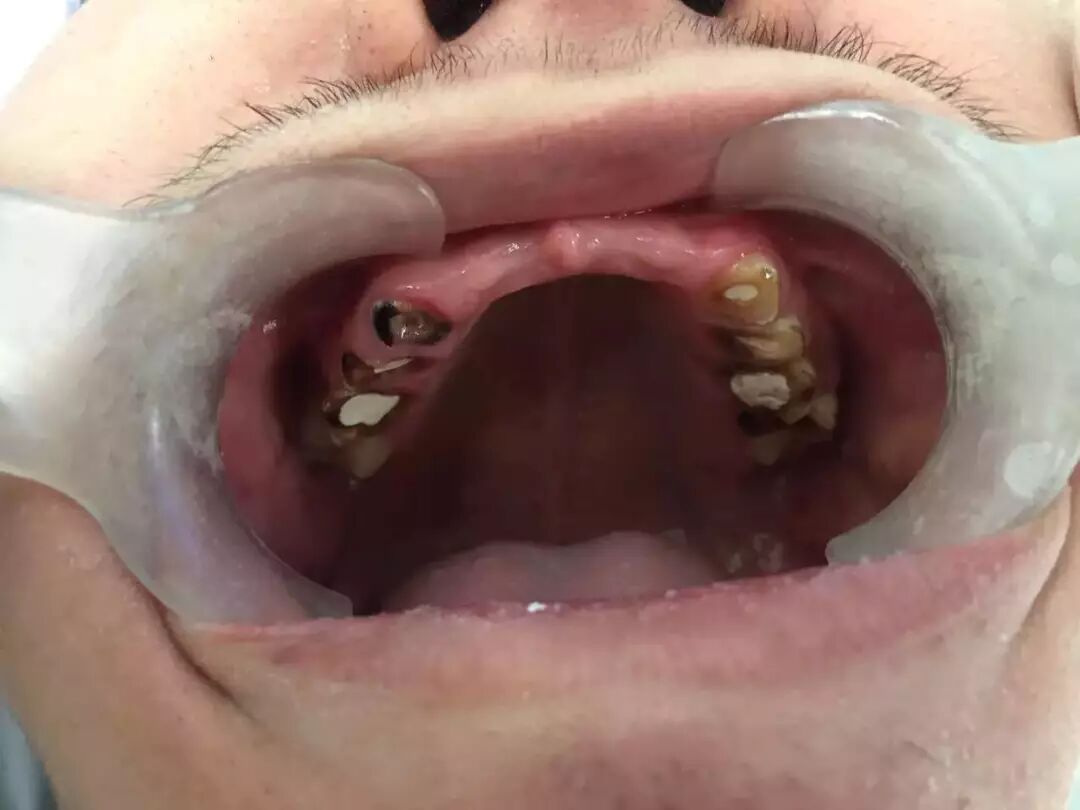

才19岁,上面六颗门牙全烂光拔掉了

男孩被妈妈带到章主任这里的时候,满口牙齿已经惨不忍睹。

成年人的口腔里,有功能的应该有28颗牙齿,上下12颗门牙+8颗前磨牙+8颗磨牙。

男孩的这28颗牙齿,其中上门牙6颗、下磨牙2颗,因为烂得太彻底,已不得不拔掉了。

还有8颗牙齿因为被饮料腐蚀得脆弱不堪而折断,甚至齐根折断与牙龈齐平了。

满口牙齿中,还算“有点样子”的只剩6颗下门牙,但也被腐蚀得很单薄,牙体几乎变透明了,基本上只要一咬骨头,也会马上碎裂。